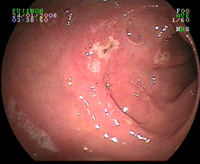

Cancer hémorragique de l'oesophage